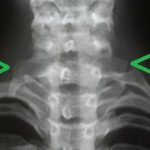

آیا دنده گردنی خطرناک است؟

دنده گردنی